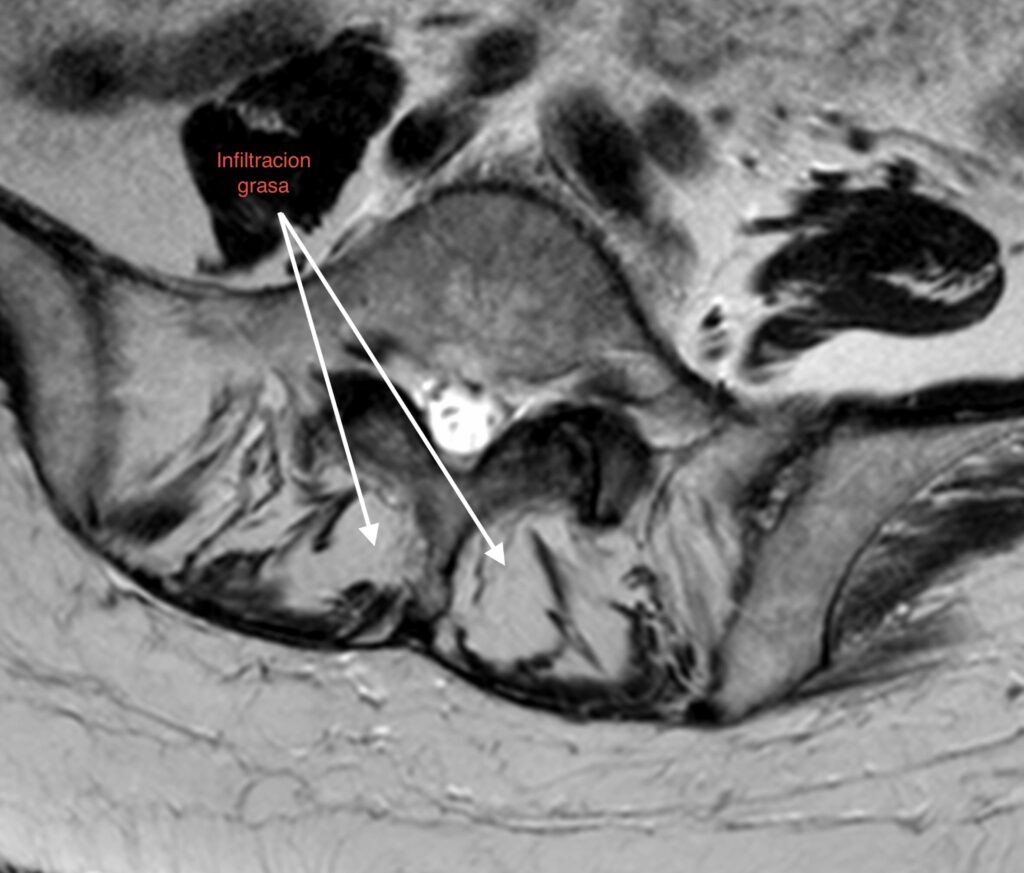

1. Pérdida del «Tirante» Dinámico: Los músculos multífidos actúan como estabilizadores segmentarios finos. En pacientes sarcopénicos, estos músculos son reemplazados por tejido adiposo no contráctil, perdiendo su capacidad de tensión.

• Calidad vs. Cantidad: La infiltración grasa (clasificación de Goutallier o medición de unidades Hounsfield en TAC) en el multífido es un factor de riesgo independiente para la reintervención. Músculos con alta infiltración grasa se correlacionan con peores resultados funcionales (ODI) y mayor tasa de complicaciones mecánicas como la cifosis de la unión proximal (PJK).

1. Screening Preoperatorio Rutinario: La RM lumbar debe utilizarse para evaluar la calidad muscular (corte axial en L3/L4), no solo la patología neural.

La sarcopenia y la infiltración grasa paravertebral no son hallazgos incidentales del envejecimiento, sino determinantes activos en la vida útil de una artrodesis lumbar. La atrofia muscular deja al disco adyacente desprotegido frente al estrés mecánico incrementado post-fusión. Identificar y tratar la sarcopenia es imperativo para reducir la incidencia de reintervenciones y mejorar la calidad de vida a largo plazo del paciente.